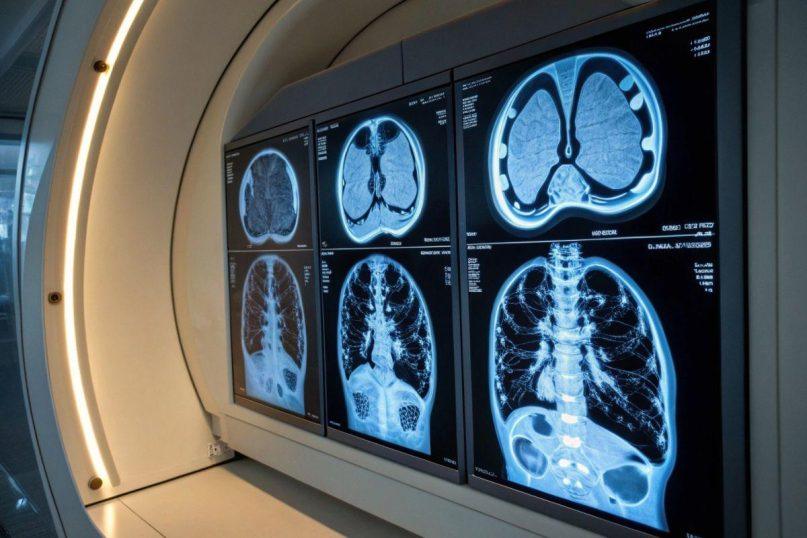

Naujas mokslinis tyrimas parodė, kad šie preparatai gali klaidinti gydytojus, vertinančius vėžio ar uždegiminių ligų požymius PET/KT (pozitronų emisijos tomografijos ir kompiuterinės tomografijos) tyrimuose.

PET/KT yra vienas svarbiausių metodų ankstyvai vėžio diagnostikai. Jis leidžia aptikti audinius su padidėjusiu metaboliniu aktyvumu – tai dažnai rodo naviką ar uždegimą.

Pasak daktaro Peterio Strouhalo iš britų kompanijos Alliance Medical, pacientams, vartojantiems GLP-1 preparatus, PET nuotraukose matomos „neįprastos FDG kaupimosi zonos“. Tai gali sudaryti klaidingus „karštuosius taškus“, primenančius naviką, arba priešingai – paslėpti tikrąsias vėžio židinių vietas.